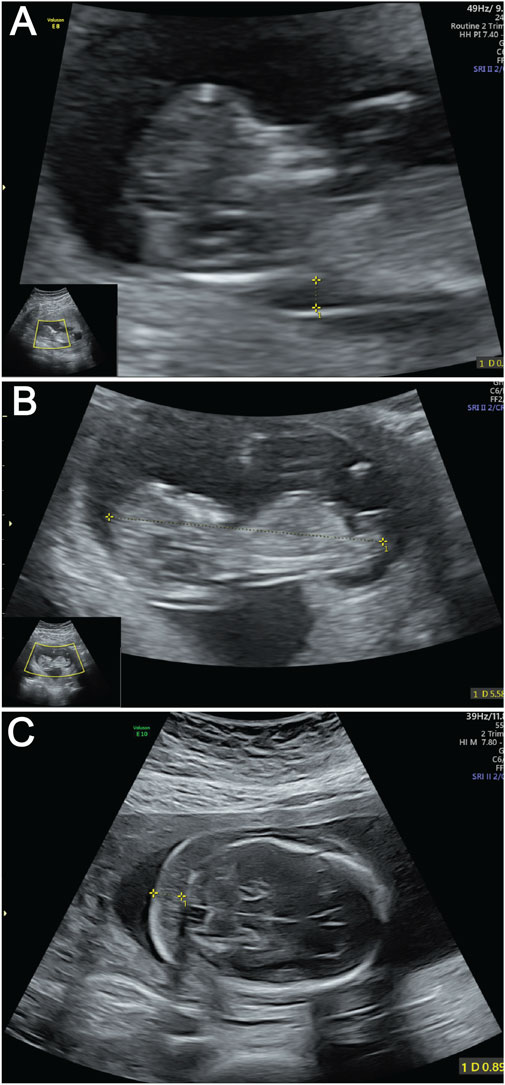

A 30-year-old primigravida (gravida 1 para 0) with regular 30-day menstrual cycles (last menstrual period: 25 October 2024) and a history of one prior fetal demise has been confirmed pregnant following amenorrhea. During first-trimester screening, a significantly increased nuchal translucency (NT) measurement of 3.4 mm was detected (Figure 1A). Fetal biometry demonstrated appropriate growth parameters for gestational age: biparietal diameter 47 mm, head circumference 188 mm, abdominal circumference 172 mm, femur length 34 mm, and humerus length 32 mm (Figure 1B).

Figure 1. Ultrasound images of fetus demonstrating key anatomical views. (A) Ultrasound measurement of NT thickness. Yellow calipers mark the NT measurement points; (B) Fetal CRL measurement by ultrasound. The dotted line between yellow calipers indicates the CRL. (C) Ultrasound evaluation of NF thickness. Yellow calipers demarcate the NF measurement area.

At the current presentation, a detailed fetal anatomical survey performed at this presentation confirmed the presence of a thickened nuchal fold measuring 9 mm (Figure 1C). Additional findings included a hyperechoic intracardiac focus (EIF) in the left ventricle, a hyperechoic uterine band bridging the anterior and posterior uterine walls (noted incidentally), and a transverse cerebellar diameter and lateral ventricular width within normal limits. Comprehensive structural evaluation confirmed normal anatomy of the fetal skull, spine, lips, extremities, stomach, kidneys, bladder, and umbilical cord insertion site. Cardiac anatomy appeared balanced with a normal four-chamber view and comparable great vessel dimensions. Fetal cardiac activity was regular at 129 beats per minute, with normal fetal movements observed. The patient’s main concern was the prior fetal demise and new ultrasound findings, which prompted referral to our fetal medicine clinic for further evaluation.